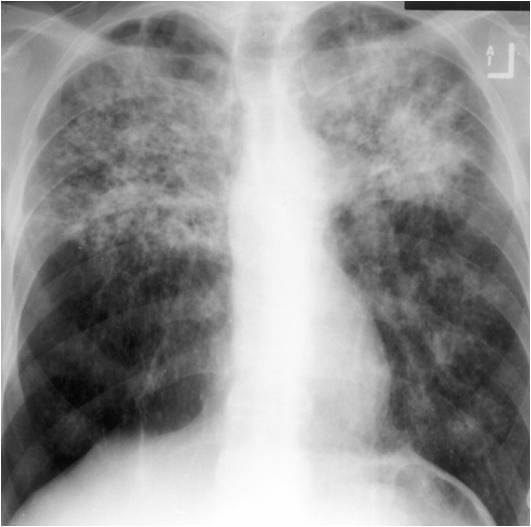

The following are examples of how Active TB may look on CXR:

Mimics any pneumonia; occurs in debilitated pts, when Mtb first enters lung, and innate immune system unable to contain it.